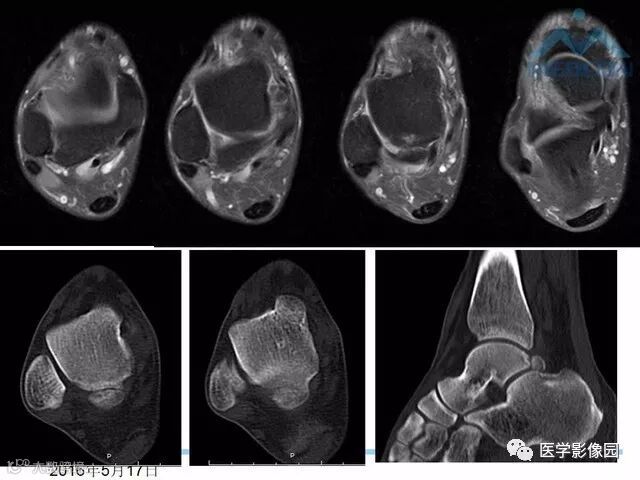

踝关节撞击综合征影像诊断,干货满满,值得收藏!

导读:踝关节撞击综合征影像诊断。干货满满,值得收藏!

踝关节撞击综合征影像诊断。干货满满,值得收藏!